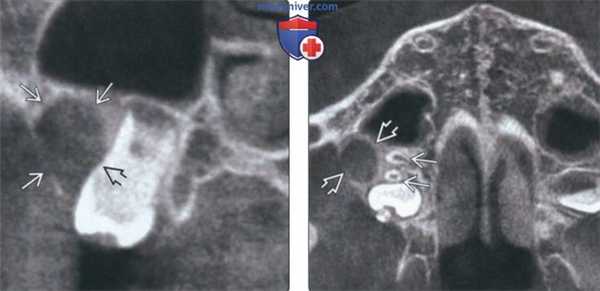

(Слева) На аксиальной КЛКТ у этого же пациента определяется вздутие и истончение щечной кортикальной пластинки, обусловленное кистой в нижней челюсти слева. Обратите внимание на смещение корней второго моляра к язычной кортикальной пластинке.

(Справа) На КЛКТ (профильный срез) у этого же пациента определяется наклон второго моляра с вклинением коронки в щечную, а вершины корня - в язычную кортикальную пластинку. Рентгеновская картина типична для БЩК. Обратите внимание на близко расположенный нижнечелюстной канал.

(Слева) На корональной КЛКТ у этого же пациента определяется БЩК, связанная со вторым моляром верхней челюсти справа. Центр кисты находится в области щечной бифуркации. Хорошо заметен наклон зуба.

(Справа) На аксиальной КЛКТ у этого же пациента определяется смещение вершин щечных корней к небу. Наклон зуба очевиден на исходной панорамной рентгенограмме, в отличие от кисты, которая изначально была пропущена.